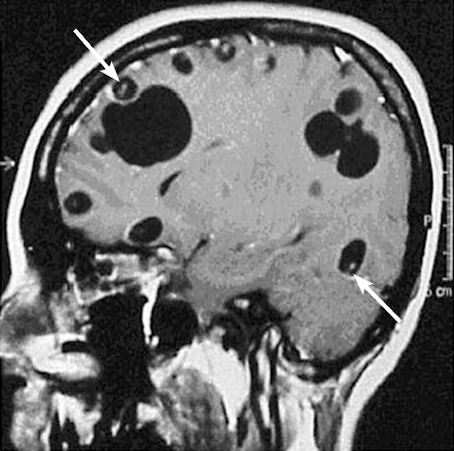

Today, we talked about the fascinating case of a middle-aged man presenting with subacute cough, night sweats, and 15 pound weight loss, found to have bilateral hilar LAD on CXR and CT concerning for pulmonary sarcoidosis. While awaiting LN biopsy, he developed L sided Bell’s palsy with MRI showing inflammation of CN5 and CN7 as well as nodular dural thickening of the trigeminal cave concerning for neurosarcoidosis. LN biopsy showed non-caseating granulomas and he was subsequently started on high dose steroids for neurosarcoidosis.

- Neurologic: Noted in 5% of cases. MRI with contrast can help with diagnosis. Complications: